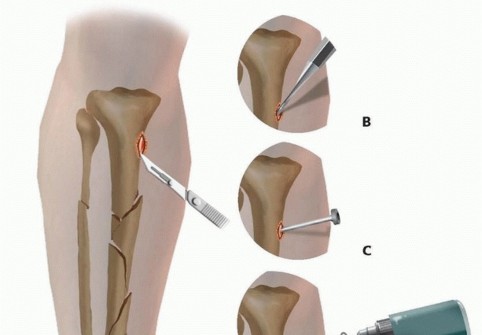

Pin Insertion Technique The correct insertion technique involves incising the skin directly at the side of pin insertion. After a generous incision is made, dissection is carried directly down to bone and the periosteum is incised where anatomically feasible ( TECH FIG 1A). A small Penfield-type elevator is used to gently reflect the periosteum off the bone at the site of insertion ( TECH FIG 1B). Extraneous soft tissue tethering and necrosis is avoided by minimizing soft tissue at the site of insertion.

### TECH FIG 1 • Proper pin insertion technique. A. A generous incision is made over the location of the pin site. B. A small elevator is used to elevate all soft tissues, including the periosteum, off the bone to help avoid the tethering of excessive soft tissues during predrilling and pin insertion. C. A trocar is advanced to bone to protect the soft tissues. D. The pin site is predrilled through the trocar to avoid incarcerating and tethering soft tissues. E,F. A T-handle insertion chuck is used to hand-torque the pin into position, achieving purchase in both the near and far cortices.

(continued)

A trocar and drill sleeve are advanced directly to bone, minimizing the amount of soft tissue entrapment that might be encountered during predrilling ( TECH FIG 1C,D). A sleeve should also be used if a self-drilling pin is selected. After predrilling, an appropriate-size depth of pin is advanced by hand to achieve bicortical purchase. Any offending soft tissue tethering should be released with a small scalpel ( TECH FIG 1E,F). Fluoroscopy is used to ensure that transcortical pin placement is avoided ( TECH FIG 1G). 537

- TECH FIG 1 • (continued) G. It is important to place the trocar over the center of the medullary canal and confirm its location to ensure that the pin captures the near cortex, medullary canal, and far cortex. This confirms that a transcortical pin is avoided, as these pins can be stress risers and may lead to pin-related fracture or pin infection due to the drilling and placement in only hard, dense cortical bone.